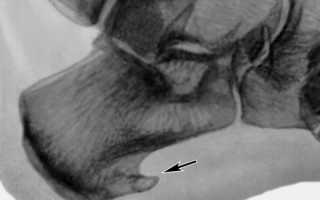

Перед проведением процедуры, проводится диагностика пациента – необходимо сделать рентгенологический снимок конечности. Рентгенограмма дает вид ноги в двух проекциях. По снимку врач определяет необходимость облучения, его периодичность, количество сеансов, нужных для получения результата. Интервал между сеансами обычно составляет от двух до нескольких дней.

После окончания восстановительного периода следует сделать повторно рентгеновский снимок, чтобы оценить наличие признаков шпоры.